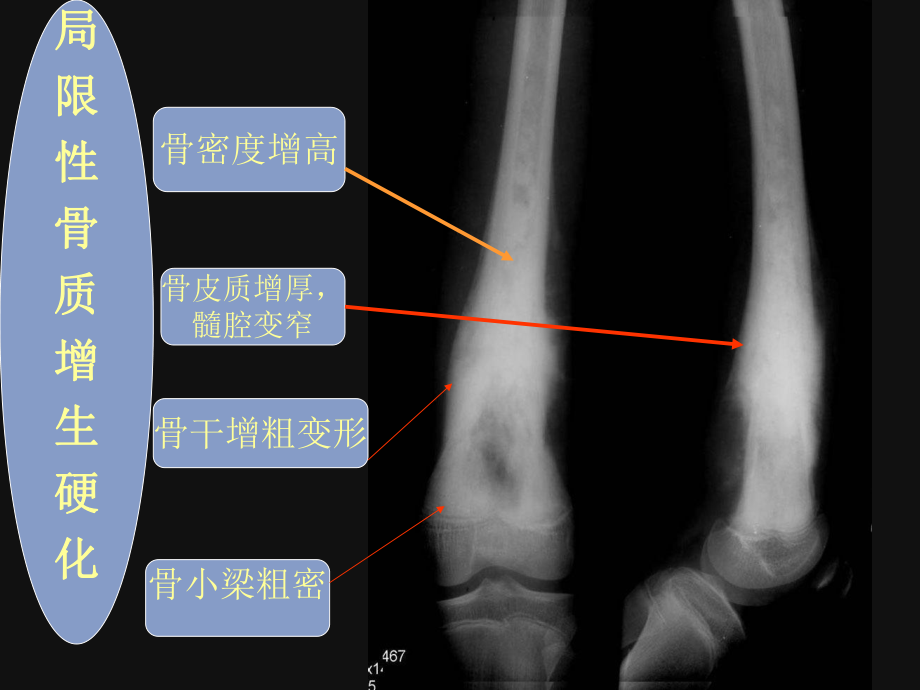

1、骨关节系统 (BONE AND JOINT SYSTEM) 临床医学临床医学2、 X线表现线表现: (1)骨密度增高;)骨密度增高; ( 2)骨皮质增厚,髓腔变窄,骨)骨皮质增厚,髓腔变窄,骨干增粗变形; (3)骨小梁粗密;)骨小梁粗密;(hyperostosis and osteoclerosis)骨的基本病变骨的基本病变局局限限性性骨骨质质增增生生硬硬化化骨密度增高骨皮质增厚,髓腔变窄骨小梁粗密骨干增粗变形骨密度骨密度骨皮质骨皮质骨髓腔骨髓腔增高增高增厚增厚变窄变窄正常正常 石骨症石骨症 广泛性广泛性 骨质密度增高骨质增生CT改变骨质增生CT改变骨皮质骨皮质骨髓腔变窄骨髓腔变窄 局部骨质因